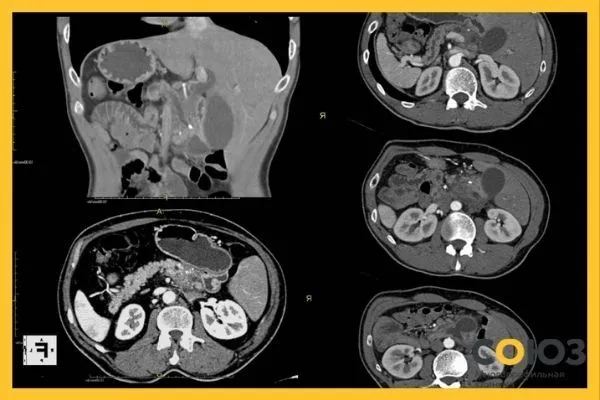

| Компьютерная томография (КТ) | Более точное объемное изображение органов | Оценка структуры и степени воспаления |

| Магнитно-резонансная томография (МРТ) | Высокоточная визуализация без облучения | Диагностика опухолей, кист, воспалений |